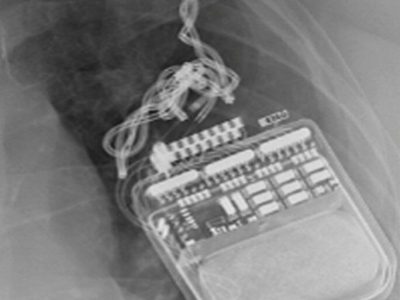

Welcome to this e-learning resource for stereotactic functional neurosurgery and DBS, with focus on visual anatomical targeting.

The aim of this website is to cover every detail of DBS that is of importance from a clinical perspective, including the most fundamental basics. The site is therefore suitable for young colleagues who are starting their training within the field of stereotactic functional neurosurgery and DBS. Hopefully, some of the lectures will also be of value to more experienced colleagues, and to nonneurosurgeons with an interest in DBS.